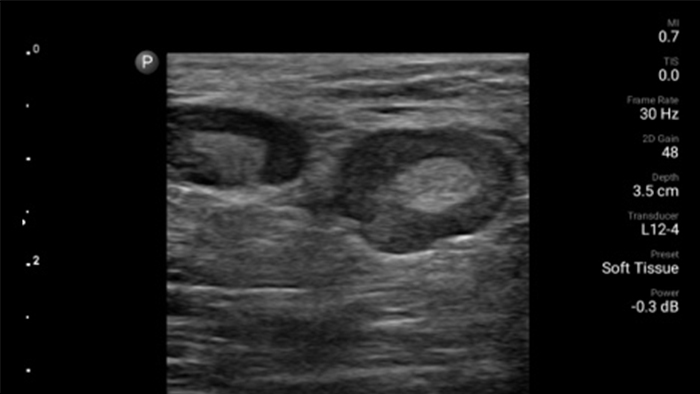

Exceptional ultrasound imaging

Lumify handheld ultrasound offers images that enhance diagnostic confidence.

See more when it counts

Lumify can help you make real-time decisions with more confidence, from assessment to recovery. Reveal the subtle details of an image, uncover enriched tissue definition with multiple angles and much more.